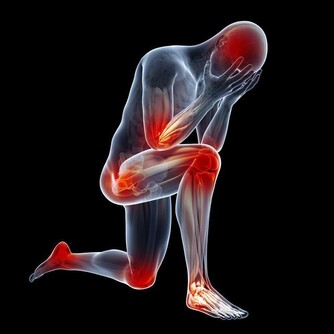

糖尿病會損害免疫系統,讓人們更容易受到感染,當糖尿病患者感染次數頻繁,或者恢復時間越來越長的時候,就應該選擇及時就醫了。

徵兆五:腎臟問題

腎功能不全,會引起腎的病變。腎的病變會讓糖尿病患者腎臟出現一定的不良反應。